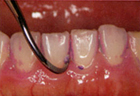

2.歯石除去

歯の表面や歯肉の中(歯根の表面)などに付着している歯石を除去します。